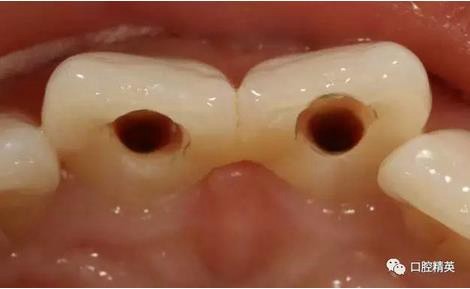

(四診)11,21唇側(cè)膿腫基本消除,叩(-),預(yù)備樁道,置入纖維樁,備牙,取模,翻制臨時(shí)冠。

可見兩側(cè)齦緣外形不平整

激光休整牙齦前后